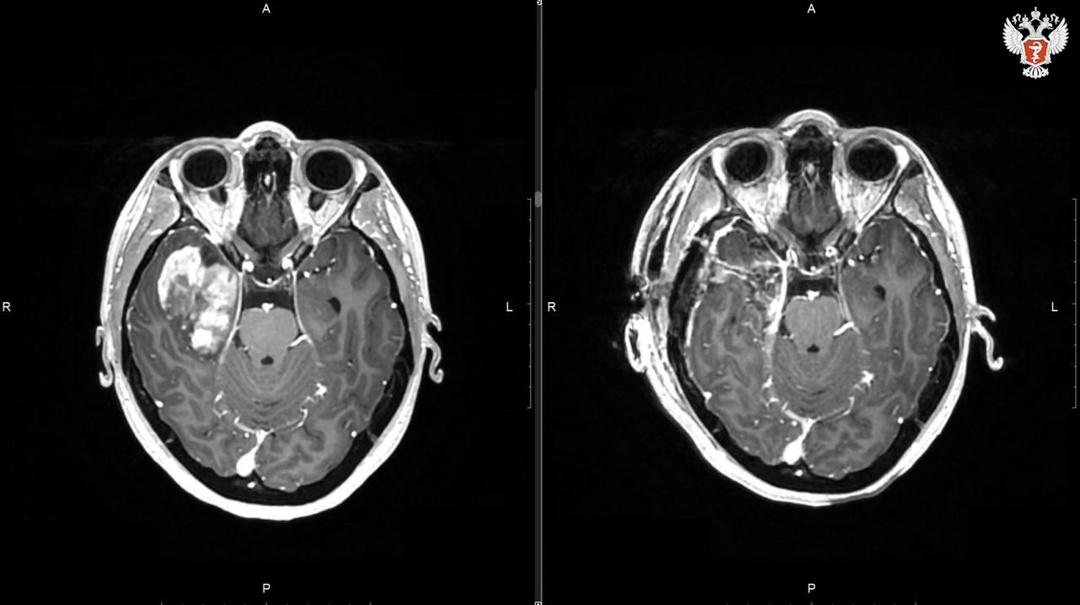

— Учитывая объём и локализацию внутримозговой опухоли — в правой височной доле — принято решение об открытом удалении опухоли. На операциях нейроонкологического профиля используется современное оборудование, навигационная техника, микроскоп, нейромониторинг. Благодаря использованию всех доступных технологий нам удалось удалить новообразование, — объясняет нейрохирург Сергей Мишинов.

Как отмечает врач, опухоль достаточно быстро росла — и к моменту операции практически достигла размера 4,5 см в диаметре. Без вмешательства новообразование продолжило бы увеличиваться, что могло привести к сдавлению здорового мозга и появлению неврологического дефицита.